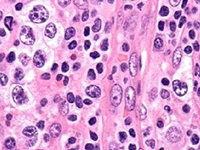

淋巴瘤是现今世界上比较常见的肿瘤之一,恶性淋巴瘤是淋巴瘤的一种,多发于青壮年。恶性淋巴瘤是发生于网状内皮系统的恶性肿瘤 , 恶性淋巴瘤分为霍奇金病 (HD) 和非霍奇金淋巴瘤 (NHL) 两大类……在[详细]

淋巴肿瘤是现今世界比较常见的肿瘤之一,恶性淋巴肿瘤是淋巴肿瘤的一种,恶性淋巴瘤是淋巴结和结外部位淋巴组织的免疫细胞肿瘤,来源于淋巴细胞或组织细胞的恶变。在我国恶性淋巴瘤虽相对少见,...[详细]